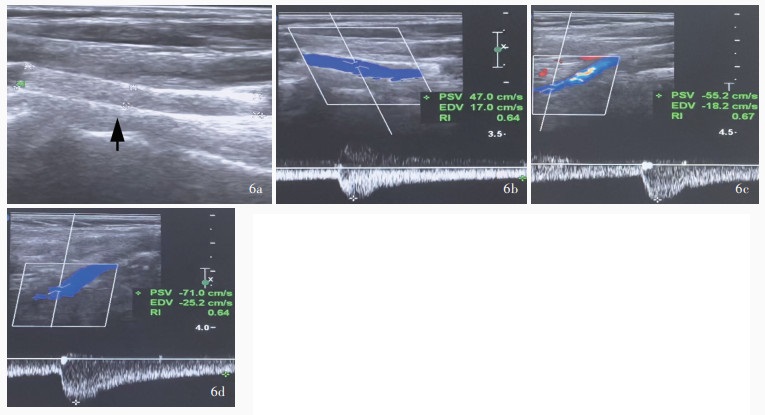

Huang WL , Deng M , Gao SJ . Ultrasound diagnosis of congenital absence of the right internal carotid artery: report of one case. Zhongguo Lin Chuang Yi Xue Ying Xiang Za Zhi, 2025, 36: 221- 222.

|

黄伟林, 邓满, 高顺记. 超声诊断右侧颈内动脉先天性缺如1例. 中国临床医学影像杂志, 2025, 36: 221- 222.